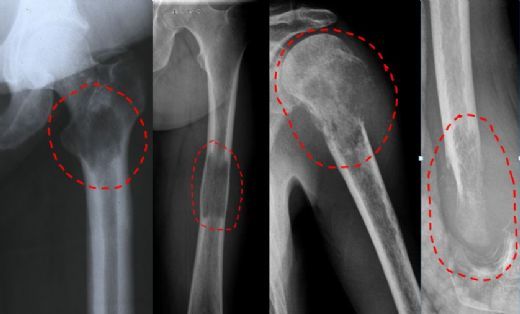

Tanı Yöntemleri Kemik tümörlerinin tanısı, klinik değerlendirme ve çeşitli görüntüleme yöntemleri ile konulmaktadır. Tanı sürecinde kullanılan başlıca yöntemler şunlardır: